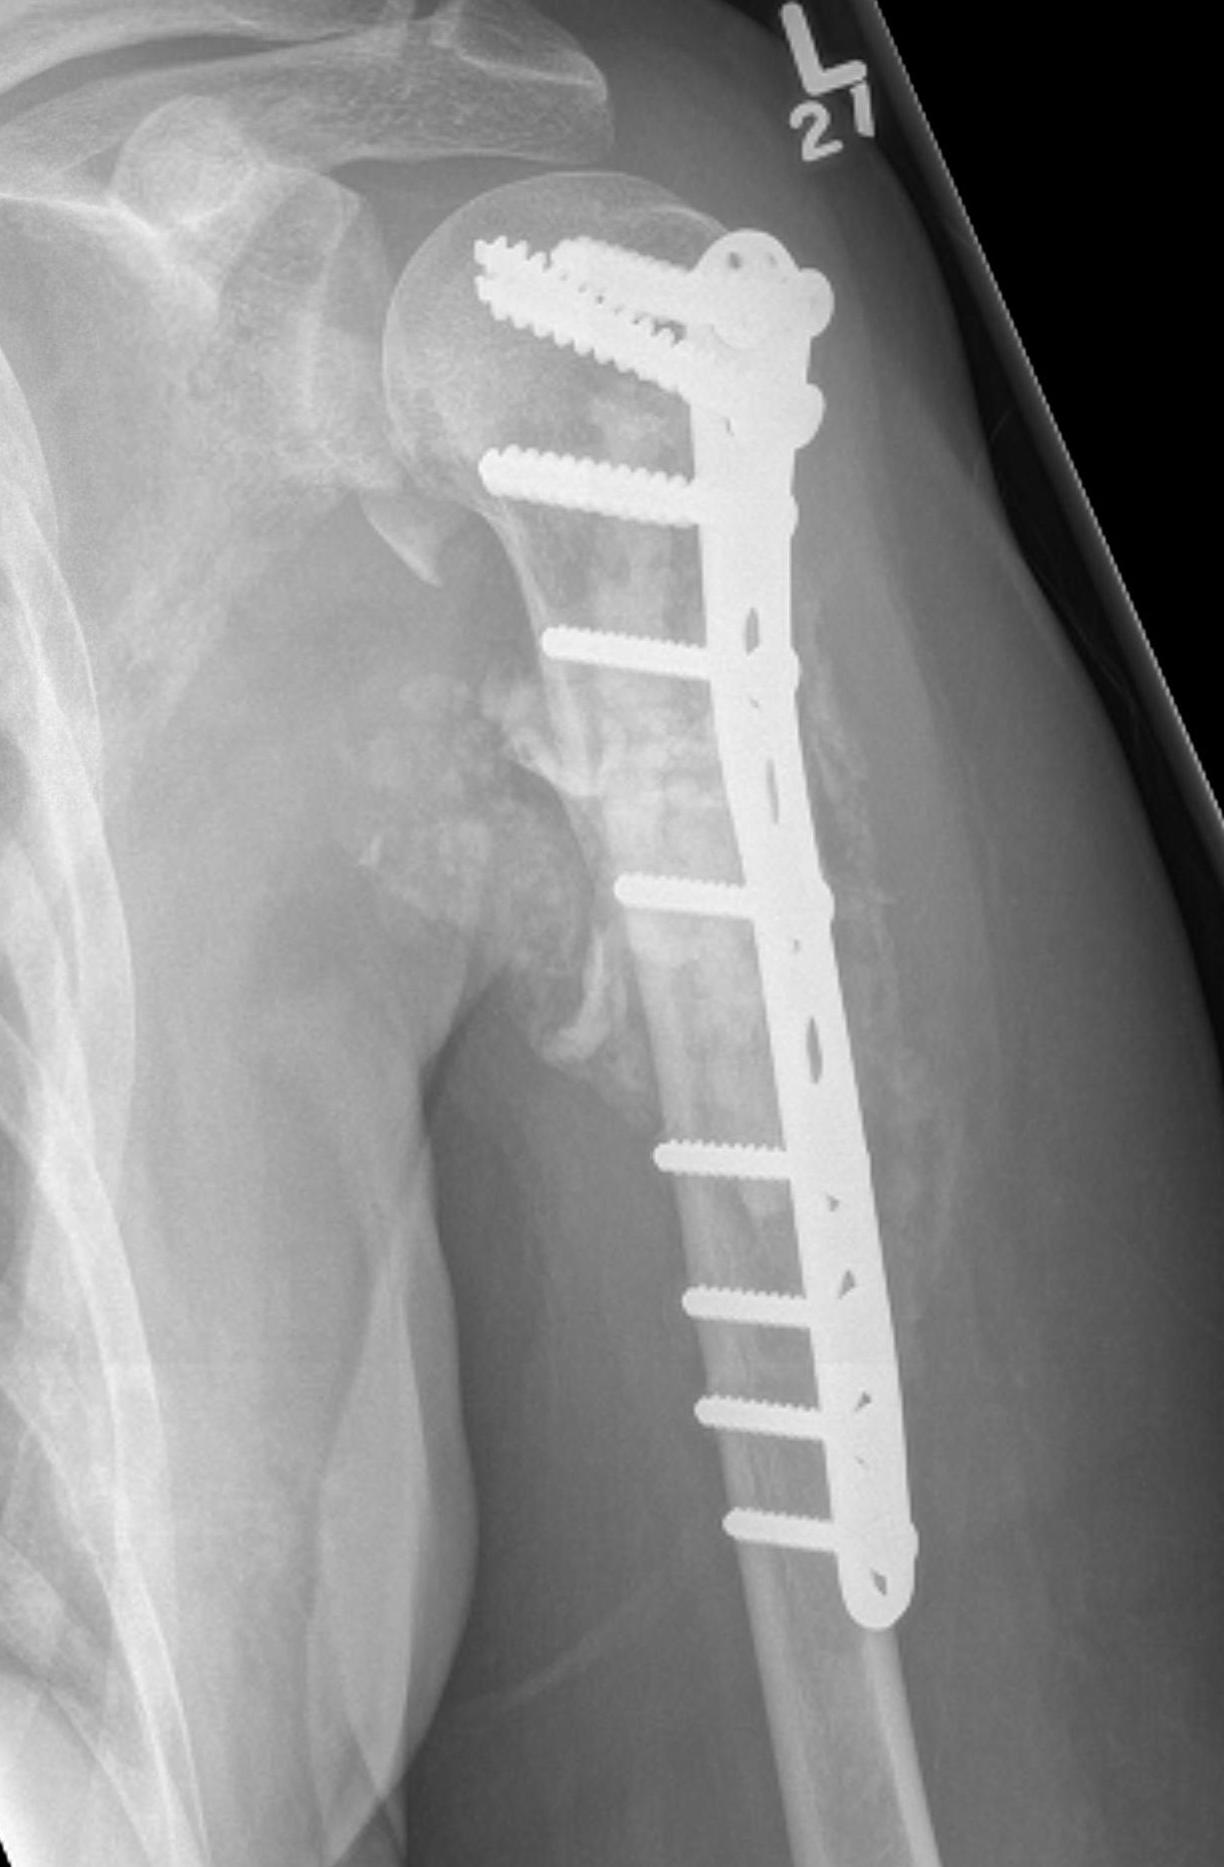

Proximal Humerus

Options

ORIF with plate +/- cement

IMN +/- cement

Tumour prosthesis

Results

Wu et al J Orthop Traumatol 2023

- 45 patients with proximal humerus metastasis

- IM nailing + cement versus plate

- lower blood loss and shorted hospital stay with IMN

- better pain relief with IMN